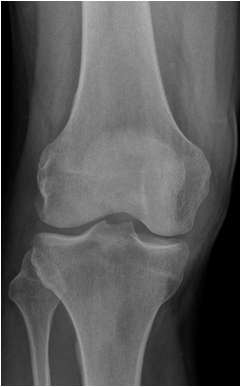

Fig. 13. A) Knee joint with degenerative changes. Note the sclerotic medial tibial plateau and joint space narrowing. A small osteophyte is seen on the medial femoral condyle. B.) Pelvis with marked degeneration of both hip joints. The right femoral head shows lateral osteophyte formation and is deformed. The joint space is narrow with increased subchondral sclerosis of the acetabular roof. The left hip has a marked joint space narrowing and lateral osteophyte formation. The femoral head shows increased density due to sclerotic areas and irregularity.